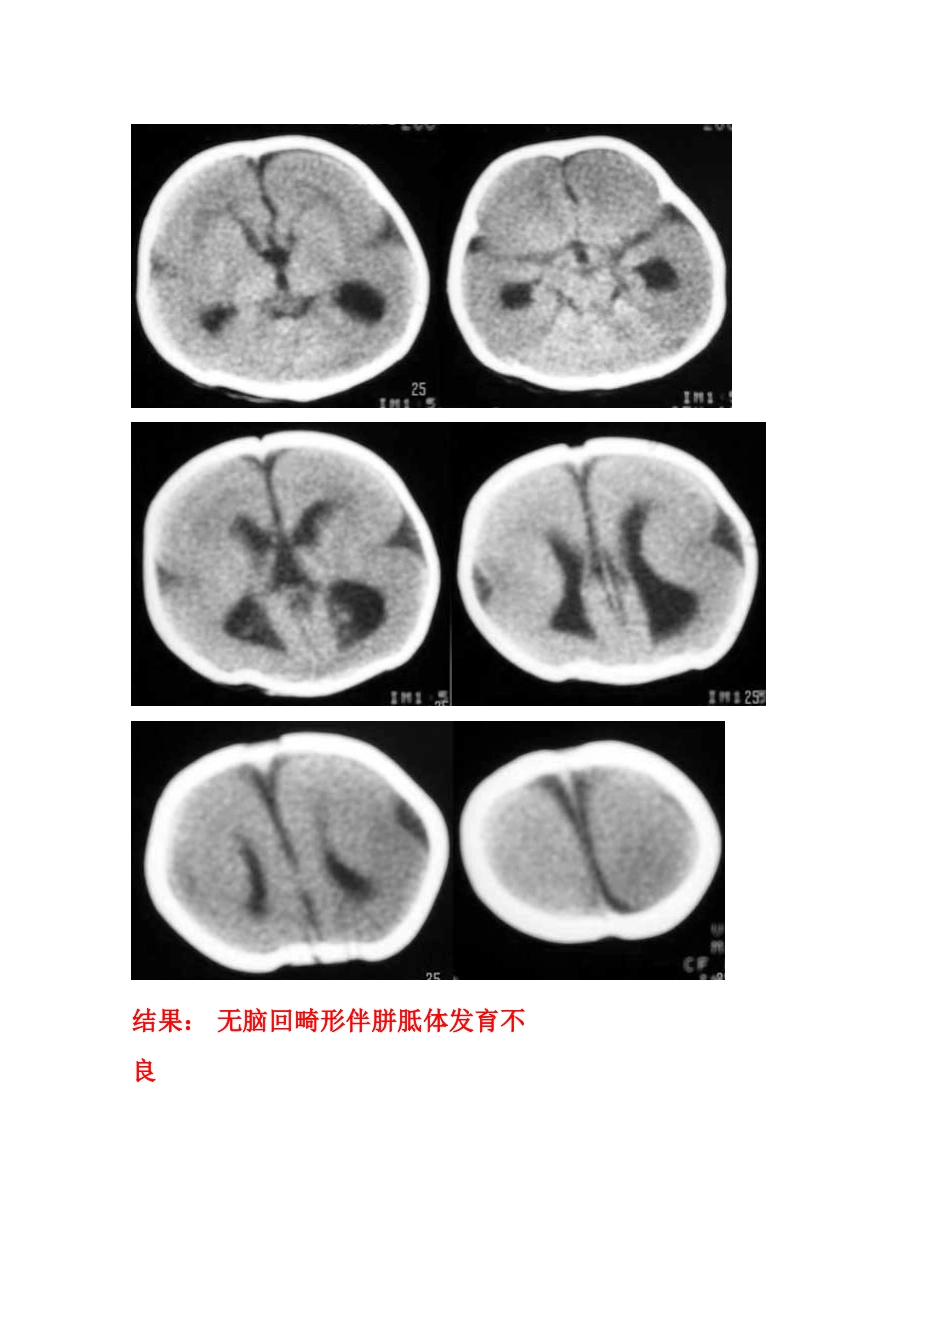

F/0.5Y。患儿主要表现为癫痫,近一个月来频发。五官尚可,头颅大小与同龄儿相比稍小,智力低下(平时家人斗小孩时目光及动做迟缓)。结果:无脑回畸形伴胼胝体发育不良男,8个月,间歇性惊厥3个月。患儿体检无明显异常发现,心肺正常。血常规正常。今日临床以脑炎?要求CT检查。平扫显示大脑半球皮质明显增厚,脑白质减少,两侧额顶脑沟少而浅,呈现巨大脑回表现,部分大脑皮质缺乏沟回,影像:巨脑回畸形。女性,22岁,左侧上下肢瘫痪21年结果:巨脑回畸形[病理]无脑回畸形和/或巨脑回畸形:无脑回畸形指大脑表面光滑,无脑回结构;巨脑回畸形指大脑停留在先天性巨脑回原始阶段,脑回宽、扁。两者仅为畸形成度不同,可同时存在于脑的不同部位。前者多在顶枕部,后者多位于额部。镜下管前者大脑皮质结构异常,皮质分层不完全或不分层,常见不成熟的神经细胞。后者皮层保留了原始皮层的4曾神经细胞结构,神经细胞分化不成熟。白质中常发现异位的神经细胞,有时呈结节状。[临床表现]无脑回畸形患儿在新生儿期常有小头畸形和轻微面部异常,以后表现出智力落后。完全性无脑回畸形者大多在2岁前死亡。巨脑回存活者常有智力低下和癫痫。[CT表现]无脑回畸形和/或巨脑回畸形,前者主要表现为脑表面光滑,脑回、脑沟消失,皮层增厚,白质减少。后者主要表现为侧裂变浅、增宽,脑回增宽,皮质增后,内表面光滑,白质减少,患侧脑室系统扩大。此外,无脑回畸形两侧裂变浅,呈“8”字形表现。[本例CT平扫]显示双侧大脑半球皮层明显增厚、表面光滑、无脑回及脑沟,皮层下白质稀少。双侧外侧裂变浅、凹陷,整个双侧大脑半球呈“8”字形表现,脑室系统扩大。前纵裂增宽、增深,与第三脑室向连通。双侧侧脑室扩大、分离。